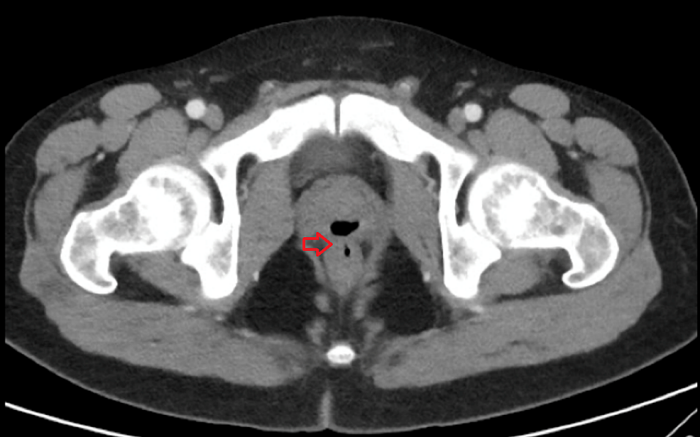

남성의 생체 신호에는 문제가 보이지 않았지만, 소변 검사에서는 요로 감염의 징후가 확인 된 것. 그후의 CT 검사를 통해, 직장과 전립섭 사이에 "가스가 찬 구조"가 존재하는 것으로 밝혀져, 직장과 요도를 연결하는 구멍 인 "직장 요도 누관"이 형성되어있는 것으로 밝혀졌다. 아래 사진에서 화살표로 표시 한 부분이, 가스에 의해 막힌 직장 요도 누관이다.

남성의 직장과 요도 관의 구멍을 통해 연결되어 있었기 때문에, 본래라면 요도에서 나올 소변이나 정액이 직장으로 흘러들어가거나 직장의 변이 요도까지 흘러들어오게 되었다는 것.